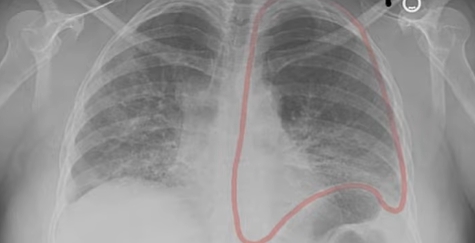

✔ 흉부 CT에서 이상 소견이 나온 경우